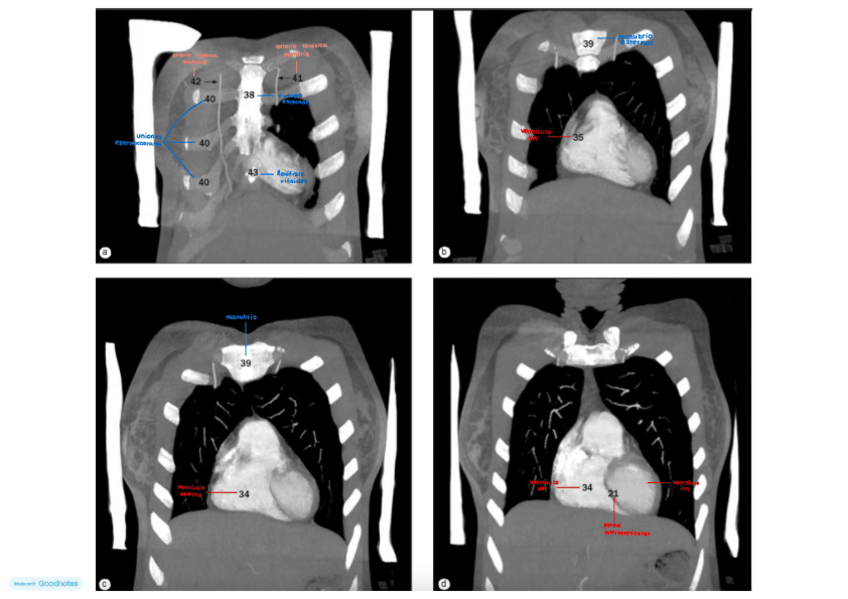

IMAGENES-TORAX-CORONAL-con-antomia.pdf